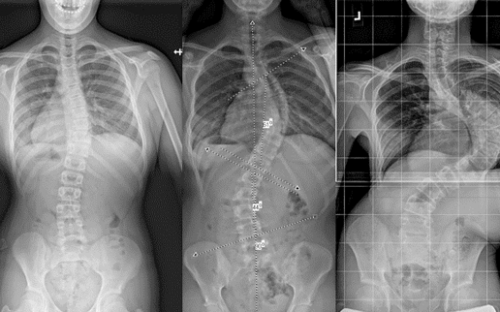

يعاني بعض المراهقات من انحناء غير طبيعي للعمود الفقري يُعرف بـ اعوجاج العمود الفقري. غالبًا ما يلجأ الأطباء إلى الحزام الطبي كحل غير جراحي لتقويم الانحناء ومنع تفاقمه.

أجريت دراسة شملت 350 مراهقة مصابة بـ اعوجاج العمود الفقري. جميعهن استخدمن الحزام الطبي وتم متابعة النتائج على مدى فترة معينة. تم تصنيف المراهقات حسب وزن الجسم إلى مجموعتين: منخفضة الوزن وطبيعية الوزن أو أعلى.

التحليل الإحصائي أظهر أن انخفاض الوزن مرتبط بشكل كبير بفشل العلاج، مما يجعل وزن الجسم عاملاً مهمًا عند وصف حزام اعوجاج العمود الفقري.

التطور الكبير في تصميم الأحزمة الطبية جعل علاج اعوجاج العمود الفقري عند المراهقين أكثر نجاحًا وأقل إزعاجًا. باستخدام تقنيات التصوير الثلاثي الأبعاد والمحاكاة الرقمية، أصبح الحزام أكثر خفة وراحة، ويعطي نتائج أفضل في تصحيح الانحناء والتواء العمود الفقري.